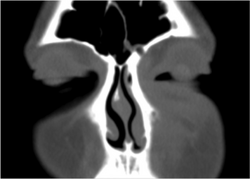

If the diagnosis is unclear, a CT scan may be done to rule out other possibilities.

Periorbital cellulitis must be differentiated from orbital cellulitis. In contrast to orbital cellulitis, periorbital cellulitis do not have bulging of the eye (proptosis), limited eye movement (ophthalmoplegia), pain on eye movement, or loss of vision.